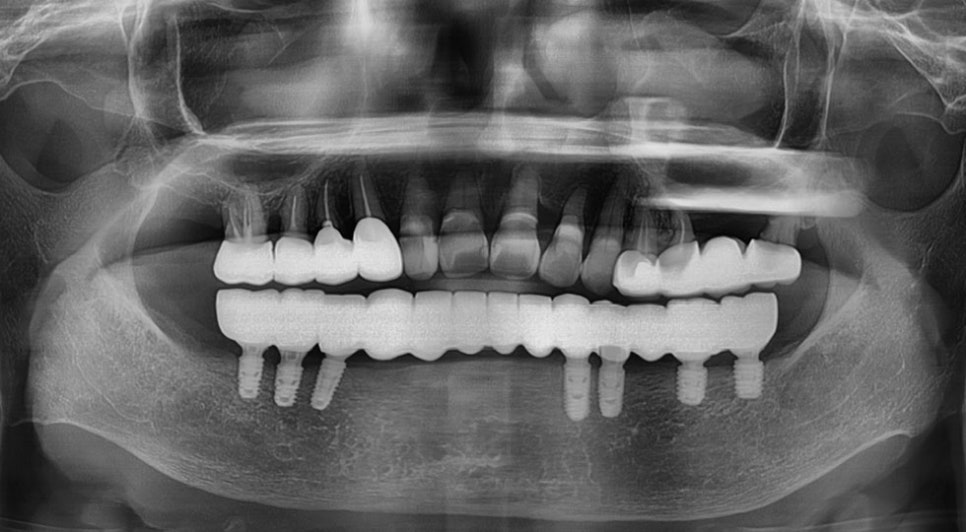

위의 사진은 3D로 CT를 컴퓨터 분석하는

모습이며 이렇듯 강남임플란트잘하는치과

본 치과에서는 임플란트 치료의 전 과정을

디지털로 진행하고 수술 전 3D 모의 수술을

통해 알맞은 수술 경로를 찾아

골조직과 신경 위치 등을 명확히 파악하여

신속하고 안정적인 수술 경로로 진행합니다.

따라서 개인의 구강 구조와 잇몸뼈에

알맞은 식립 위치와 각도, 깊이까지

파악하여 튼튼하게 치료할 수 있습니다.

뉴엔치과만의 디지털 임플란트 센터

임플란트 치료는 다른 치료에 비해

굉장히 세밀한 치료이기 때문에 정밀한

3D 디지털 기술이 접목된다면

의료진 판단에만 의존하는 기존

임플란트 치료를 더욱 명확하게 예측하고

오차범위가 거의 없이 치료할 수 있습니다.

강남임플란트잘하는치과 본 치과에는

수많은 디지털 임상 경험을 보유한

의료진들의 수준 높은 디지털 치료가

가능한 곳입니다. 치과의 모든 장비가

디지털 시스템으로 구축되어 있으며

이러한 디지털 치과 장비를 이용한

1:1 개인 보철물을 디지털로 제작하고

오차 없는 임플란트 식립을 위해

컴퓨터 모의 치료를 진행합니다.

개인의 구강 정보를 빠르고 명확하게

스캔하기 위해 3D 구강 스캐너를 이용하고

3차원 데이터를 통해 정밀한 3D-CT 촬영을

진행하고 있습니다.